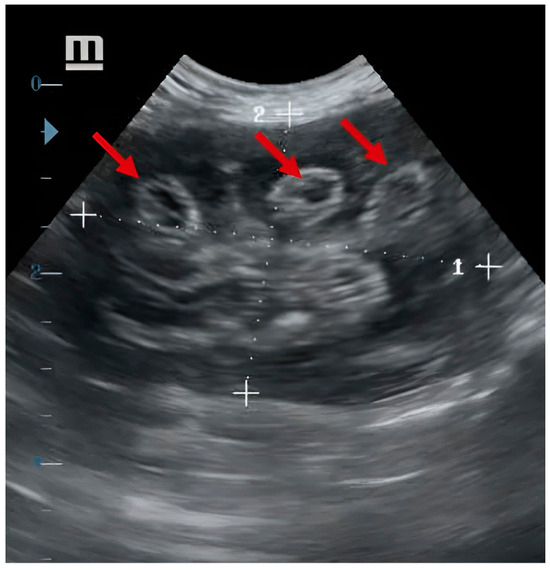

Since the adoption, the puppy has been fed commercial dog food. However, the precise diet of the puppy during its first months in Delta del Tigre is unknown. During the physical examination, the animal had a normal temperature, and healthy mucous was observed. The puppy presented no pain upon abdominal palpation, and no lesions on the penis were detected. The prescribed initial treatment was amoxicillin with clavulanic acid in an oral dose of 12.5 mg/b.w. every 12 h. Four days after the initial examination, the animal returned to the clinic for a renal ultrasound. The ultrasound revealed an altered right kidney, and in its topography, circular-shaped structures in the cross-section, both in the cortex, medulla, and pelvis, these formations when incised longitudinally; meanwhile, the left kidney showed normal features. The ultrasound findings suggested parasitism by D. renale (Figure 2).

Figure 2. Ultrasound showing D. renale (red arrows) in the right kidney.